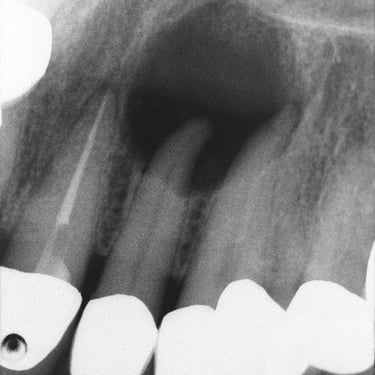

Lesión Endo-Perio Combinada

Una lesión endo-perio combinada es una condición en la que hay tanto una infección de la pulpa como una enfermedad periodontal.

Los pacientes pueden experimentar dolor, hinchazón y movilidad dental.

El tratamiento incluye tanto el tratamiento de conducto como el tratamiento periodontal para abordar ambas infecciones. La coordinación entre el endodoncista y el periodoncista es esencial.